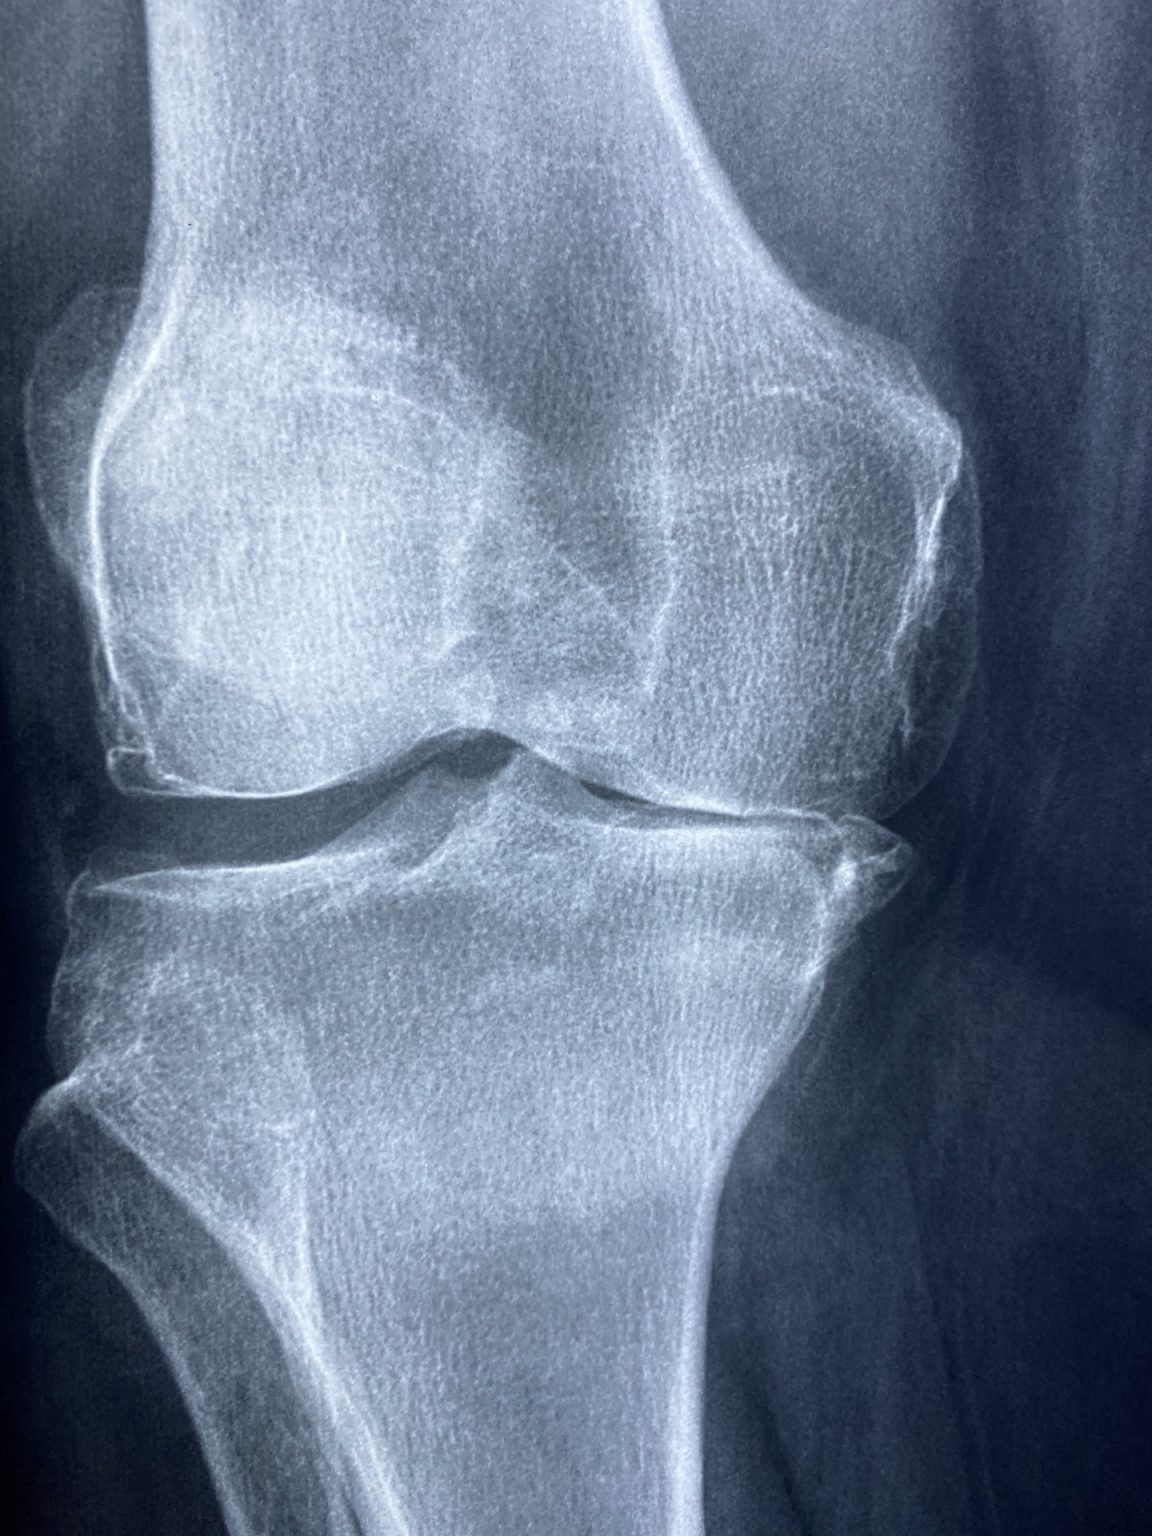

Do The Twist A Look at a Torn Meniscus

Do The Twist A Look at a Torn Meniscus Running Injured Meniscus The most common mistake runners make is jumping back into running too quickly. the most common cause for a meniscus tear in running is a sudden knee twist. Repeated stress can weaken the cartilage, making it more susceptible to injury. Can i run with a torn meniscus? For an exercise plan to be effective, it has to start at. Running Injured Meniscus.